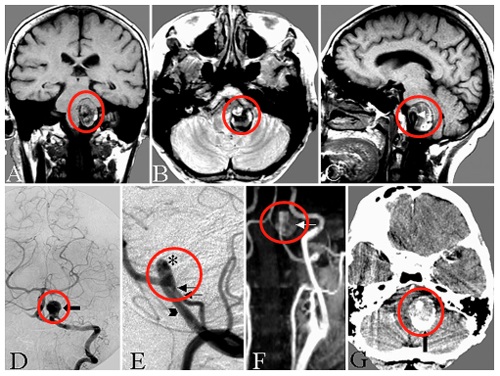

47歲的陳先生在家中突然感到劇烈頭痛,隨即陷入昏迷。家人緊急送醫(yī)后,急診CT檢查給出了令人揪心的結(jié)果:彌漫性蛛網(wǎng)膜下腔出血(圖A),而進(jìn)一步的血管造影揭開了真兇...... CT顯示彌漫性蛛網(wǎng)膜下腔出血,左側(cè)腦橋前池增厚明顯。 陳先生47歲動脈瘤 病情階段: 出血后第18天,待陳先生狀況穩(wěn)定后,...

47歲的陳先生在家中突然感到劇烈頭痛,隨即陷入昏迷。家人緊急送醫(yī)后,急診CT檢查給出了令人揪心的結(jié)果:彌漫性蛛網(wǎng)膜下腔出血(圖A),而進(jìn)一步的血管造影揭開了“真兇”......

CT顯示彌漫性蛛網(wǎng)膜下腔出血,左側(cè)腦橋前池增厚明顯。

出血后第18天,待陳先生狀況穩(wěn)定后,醫(yī)生進(jìn)行了腦血管造影檢查(圖B)。結(jié)果顯示,左側(cè)大腦后動脈P1-P2段出現(xiàn)異常擴(kuò)張伴狹窄——這是夾層動脈瘤的特征表現(xiàn)。

出血后18天血管造影顯示左側(cè)P1-P2段擴(kuò)張伴狹窄特征,顳后動脈自狹窄病變遠(yuǎn)端發(fā)出(箭頭標(biāo)注)

醫(yī)生通過左側(cè)顳下入路,選擇后顳動脈作為受體(圖C、D),成功完成搭橋和孤立術(shù),整個手術(shù)過程如同在“萬丈懸崖邊繡花”,每一步都要求精準(zhǔn)到毫米,既要避免損傷周圍神經(jīng)和血管,又要保證吻合口毫無滲漏。

C、D.選擇顳后動脈(箭頭標(biāo)注)作為受體動脈,經(jīng)左側(cè)顳下入路用連續(xù)縫合行顳淺動脈-顳后動脈吻合;

術(shù)后1周復(fù)查頸外動脈血管造影顯示,通過新建的分流血管,左側(cè)大腦后動脈供血區(qū)血流完全通暢(圖E箭頭標(biāo)注),沒有出現(xiàn)任何缺血跡象。

術(shù)后1周頸外動脈血管造影顯示,通過分流血管,整個左側(cè)大腦后動脈供血區(qū)血流良好(箭頭標(biāo)注)。